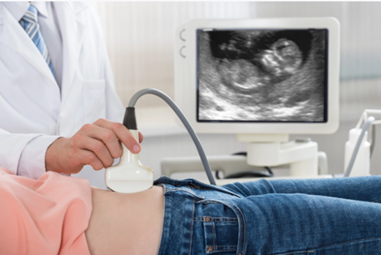

Как называется прибор, изображённый на рисунке?

1) аппарат УЗИ

2) спирометр

3) флюорограф

4) фонендоскоп

Ответ:

1

2) флюорограф

3) тонометр

4) спирометр

2